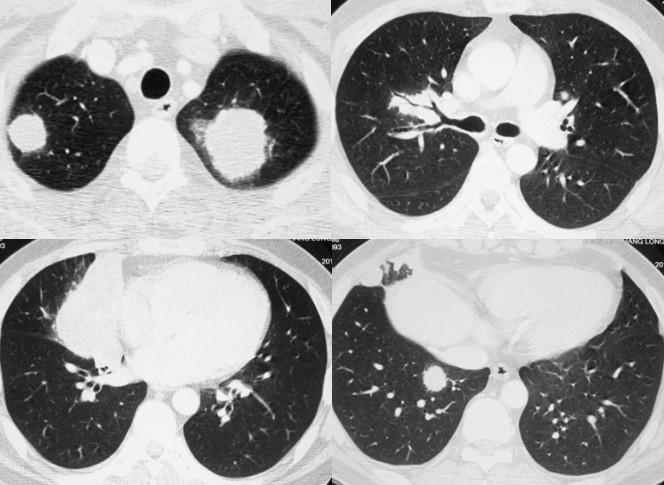

多发空洞性病灶

影像学表现为肺实质内多发空洞阴影,可合并斑片状实变影或结节影。

这个病人表现为多发病变,在实变内可以看到空洞样改变,这种空洞很漂亮,为典型的空气新月征。诊断比较明确,这个病人有免疫抑制的状态,为真菌感染。

病例1:肺结核

X线胸片表现为在两侧中上肺有斑片状阴影,隐约可以看到小的空洞样病变。CT显示的很清楚,可以看两肺尖空洞,周围有小的点状播散病灶。在上叶前段、左上叶尖后段也有空洞,这些空洞的周围可以看到树芽征,小叶中心的病变。所以这是典型的以中上肺分布的伴支气管播散病灶,为典型的肺结核病变。

病例2:奴卡氏菌感染

这个病人是肾病综合症,激素治疗,发烧。两肺可以看到类似于结节样病变,还有一些空洞性病变。CT能够明显看到液化坏死、空洞形成。这样就要考虑到感染性病变,特别是要想到真菌感染的可能。患者有免疫受损,空洞内液化很明显,而且似乎可以看到气液平面。这样真菌感染的可能性较小,因为真菌感染往往出现空洞,但是空洞不太容易液化,因为它是一种凝固性坏死。这个病人最终诊断为奴卡氏菌感染。

病例3:肺腺癌转移瘤

多发的空洞,但是结节的大小不等,大的可以看到有空洞形成,还有左肺的容积明显缩小,左下叶缺如(术后)。这个病人诊断为肺腺癌两肺转移。

多发结节和肿块影

影像学表现为多发圆形或类圆形阴影,大小不等。

病例1:重症肺炎

男,28岁,发热一周,咳嗽气短2天。虽然很年轻,但是住院时的病情很严重。虽然右上肺有斑片实变影,但两肺有广泛不规则的结节。CT显示的大多数边界不清晰,边缘有些类似磨玻璃影,右上叶可以看到磨玻璃样改变。这是不规则结节,不像肿瘤性病变呈边界比较清楚、比较圆的结节。这个病人的诊断是重症肺炎,调整治疗后效果很好。

病例2:曲霉菌感染

血液病病人,治疗后发烧。两肺多发结节,大的团块可以看到充气支气管征,实际上这是一个实变影,有大肿块和小结节。血液病的病人治疗后,如果出现这样的结节,首先想到真菌感染。这个病人最后诊断是曲霉菌感染。

病例3:GPA(肉芽肿性多血管炎)

这是一个发烧的病人。CT显示左肺尖有肿块,右肺尖有结节,在膈角区可以看到团块影,右下叶在膈肌下面可以看到结节影。在右肺门也可以看见这种改变,实变边界比较清楚,中间可以看到充气支气管征。像这种不是都是一个肿块,因为肿块主要是一种占位性病变,支气管应该变细或者消失。所以出现这种病变应该想到有肺泡填充性的病变,病人发烧,除了考虑感染外,还要想到非感染。这个病人最终诊断的是GPA。